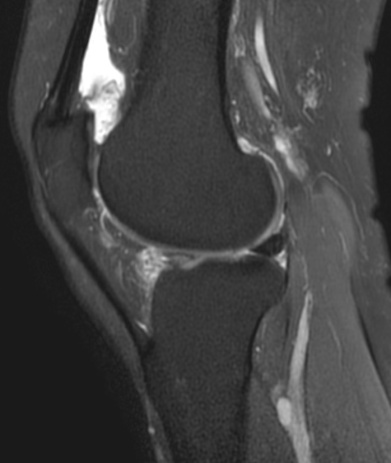

3. MRI检查:MRI在神经系统疾病的诊断中优势显著,对于脑肿瘤、脑梗死、脊髓病变等的诊断准确性较高。例如,对于一些早期的脑肿瘤,MRI能够更清晰地显示肿瘤的位置、大小、范围以及与周围组织的关系,有助于制定治疗方案。在关节疾病方面,MRI可以清晰地显示关节软骨、半月板、韧带等软组织的损伤情况,对于膝关节半月板损伤、交叉韧带断裂、肩关节肩袖损伤等疾病的诊断具有重要价值。此外,MRI在乳腺疾病、盆腔疾病等方面也有广泛的应用。

脑肿瘤T1WI+C、右膝外侧半月板撕裂、右侧膝前交叉韧带断裂、右侧肩袖损伤